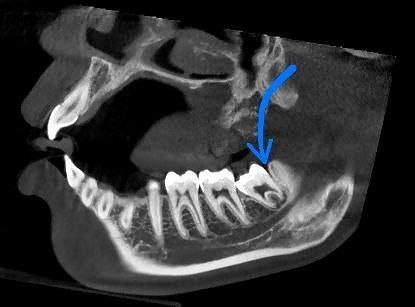

3. Ретенированные зубы мудрости.

Это зубы, которые не прорезались и остаются в кости. Они могут не вызывать проблем, но иногда требуют удаления, если создают давление на соседние зубы.

4. Дистопированные зубы мудрости.

Зубы могут расти под углом или в неправильном направлении, что может привести к смещению соседних зубов.